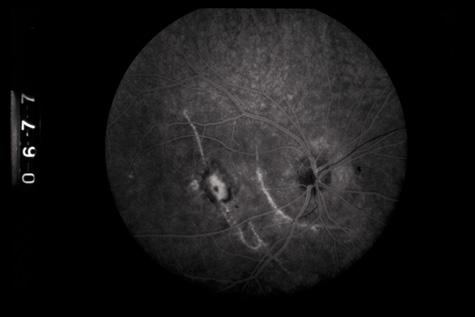

Fig. 1. A: Coup injury. At the site of impact of a stick, subretinal and vitreous hemorrhage are present. B: Three months later, most of the hemorrhage has cleared, revealing choroidal and pigment epithelial necrosis.

Commotio retinae (Latin, meaning retinal contusion) is a contrecoup injury. It can occur peripherally (Fig. 8) or centrally, in which case it is called Berlin's edema (Fig. 9). Immediately and for several hours after the trauma, the retina appears normal, although the patient may complain of decreased vision. Thereafter, the outer layers of affected retina become opaque. On fluorescein angiography, the opaque retina blocks background choroidal fluorescence, and in most cases there is no leakage into or under the retina (Fig. 10). For years, clinicians had difficulty explaining this blockage, because leakage is expected in conditions with edema. It was then shown in experimental animals and in human autopsy eyes that Berlin's edema is not true edema. The retinal opaqueness is the result of intracellular edema and fragmentation of the photoreceptor outer segments and intracellular edema of the underlying pigment epithelium. There is little or no intercellular fluid.66–69

Fig. 10. A: Commotio retinae in the macula. B: On the angiogram there is no leakage in the area of commotio retinae.

The visual acuity in commotio retinae varies from 20/20 to 20/400 and does not always correlate with the degree of retinal opacification. There is no known treatment. The prognosis is usually excellent except in cases with associated subfoveolar choroidal rupture and in cases with choroidal rupture with subfoveolar hemorrhage. Poor visual recovery can also be expected in cases with severe retinal pigment epithelial damage. Serous retinal detachment (Fig. 11) signals this condition, which can be confirmed by leakage of fluorescein into the subretinal space.70

Fig. 11. A: Serous detachment of the macula and intraretinal and vitreous hemorrhage after the eye was struck with a baseball. B: Three months later. The hemorrhages have cleared, revealing severe pigment epithelial necrosis. The visual acuity is counting fingers.